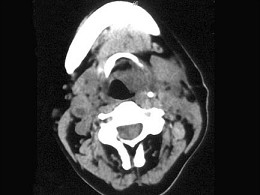

女,54岁,鼻咽部异物感约3个月,PE:左侧声带固定,可见肿物,CT如图所示,应诊断为 ( )

A.喉部乳头状瘤

B.喉癌

C.喉部血管瘤

D.慢性增生性喉炎

E.增生型喉结核

女,54岁,鼻咽部异物感约3个月,PE:左侧声带固定,可见肿物,CT如图所示,应

[单选题]女,54岁,鼻咽部异物感约3个月,PE:左侧声带固定,可见肿物,CT如图所示,应诊断为()。A . 喉部乳头状瘤B . 喉癌C . 喉部血管瘤D . 慢性增生性喉炎E . 增生型喉结核

女、54岁,鼻咽部异物感约三个月,PE:左侧声带固定,可见肿物,CT如图所示,应

[单选题]女、54岁,鼻咽部异物感约三个月,PE:左侧声带固定,可见肿物,CT如图所示,应诊断为()A .喉部乳头状瘤B .喉癌C .喉部血管瘤D .慢性增生性喉炎E .增生型喉结核

女,54岁,喉部异物感约3个月,PE:左侧声带固定,可见肿物,CT如图,最可能的

[单选题]女,54岁,喉部异物感约3个月,PE:左侧声带固定,可见肿物,CT如图,最可能的诊断是()A . 喉部乳头状瘤B . 喉癌C . 喉部血管瘤D . 慢性增生性喉炎E . 增生型喉结核

女、54岁,鼻咽部异物感约三个月,PE:左侧声带固定,可见肿物,CT如图所示,应诊断为()<img border="0" style="width: 182px;

[单选题]女、54岁,鼻咽部异物感约三个月,PE:左侧声带固定,可见肿物,CT如图所示,应诊断为()A.喉部乳头状瘤B.喉癌C.喉部血管瘤D.慢性增生性喉炎E.

女,54岁,喉部异物感约3个月,PE:左侧声带固定,可见肿物,CT如图,最可能的诊断是()<img border="0" style="width: 260px;

[单选题]女,54岁,喉部异物感约3个月,PE:左侧声带固定,可见肿物,CT如图,最可能的诊断是()A.喉部乳头状瘤B.喉癌C.喉部血管瘤D.慢性增生性喉炎E.

女,54岁,喉部异物感约3个月,PE:左侧声带固定,可见肿物,CT如图,最可能的诊断是()<img border="0" style="width: 260px;

[单选题]女,54岁,喉部异物感约3个月,PE:左侧声带固定,可见肿物,CT如图,最可能的诊断是()A.喉部乳头状瘤B.喉癌C.喉部血管瘤D.慢性增生性喉炎E.